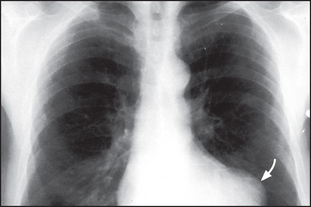

Figure 8.5 Alveolar pulmonary oedema When the pulmonary venous pressure reaches 30 mmHg, oedema fluid will pass into the alveoli. This causes shadowing (patchy to confluent depending on the extent) in the lung fields. This usually occurs first around the hila and gives a bat’s wing appearance. These changes are usually superimposed on the interstitial oedema. A lamellar pleural effusion (arrow) is seen at the right costophrenic angle where Kerley ‘B’ lines are also evident.